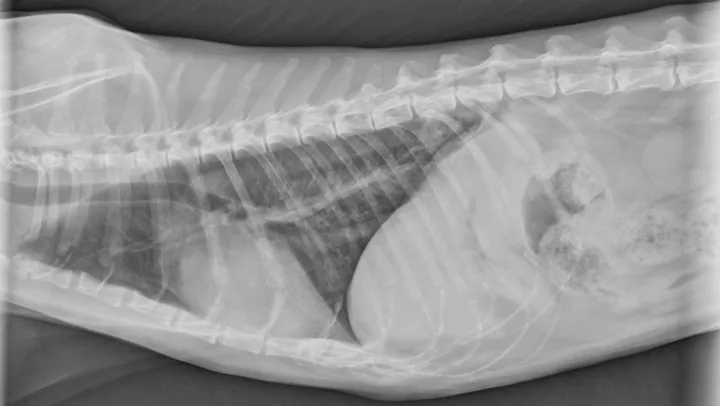

Figure 1

Lateral thoracic radiograph of a 14.5-year-old male domestic cat with a caudal dorsal cavity primary lung mass. Image courtesy of Rachel Moon, DVM, DACVR

Reported primary lung tumors (Figures 1 and 2) include squamous cell carcinoma and sarcoma, but adenocarcinomas are reportedly the most common histopathologic diagnosis.2 Adenocarcinomas are subcharacterized by location (ie, bronchial, bronchioloalveolar, alveolar) and grade. Carcinomas are graded on histopathology as differentiated or undifferentiated, with the grade directly correlating with metastatic incidence.1,3 Although most primary carcinomas are localized and solitary at diagnosis,1,4 the literature suggests that >50% of undifferentiated carcinomas and 90% of squamous cell carcinomas metastasize,1,3 with one study reporting ≈75% of feline lung tumors as metastatic.4 Metastasis to the lungs, skin, CNS, and digits may occur transpleurally, hematogenously, or via lymphatics or airways.1,3,4